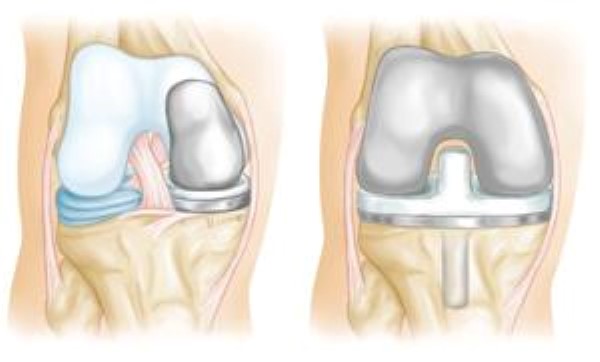

Total knee replacement or partial (unicompartmental) knee replacement (arthroplasty). Your doctor will remove the damaged cartilage and bone, and then position new metal or plastic joint surfaces to restore the function of your knee.

uni knee replacement implant and total knee replacement implant

(Left) A partial knee replacement is an option when damage is limited to just one part of the knee. (Right) A total knee replacement prosthesis.